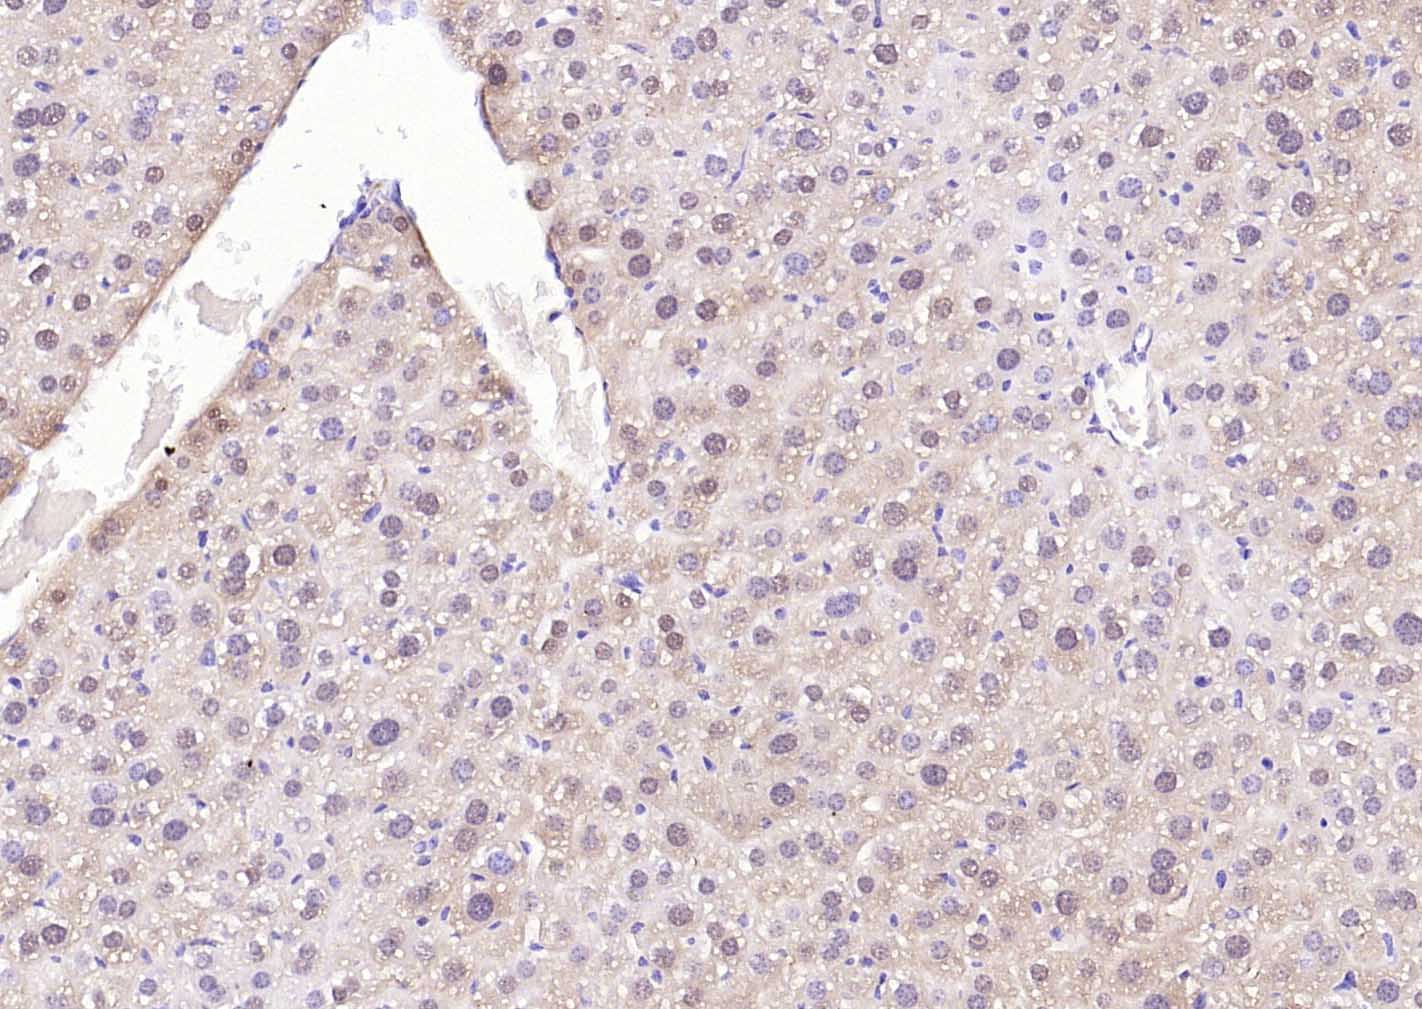

Paraformaldehyde-fixed, paraffin embedded (mouse liver); Antigen retrieval by boiling in sodium citrate buffer (pH6.0) for 15min; Block endogenous peroxidase by 3% hydrogen peroxide for 20 minutes; Blocking buffer (normal goat serum) at 37°C for 30min; Incubation with (SOD1) Monoclonal Antibody, Unconjugated (bsm-60838R) at 1:300 overnight at 4°C, followed by operating according to SP Kit(Rabbit) (sp-0023)instructionsand DAB staining.